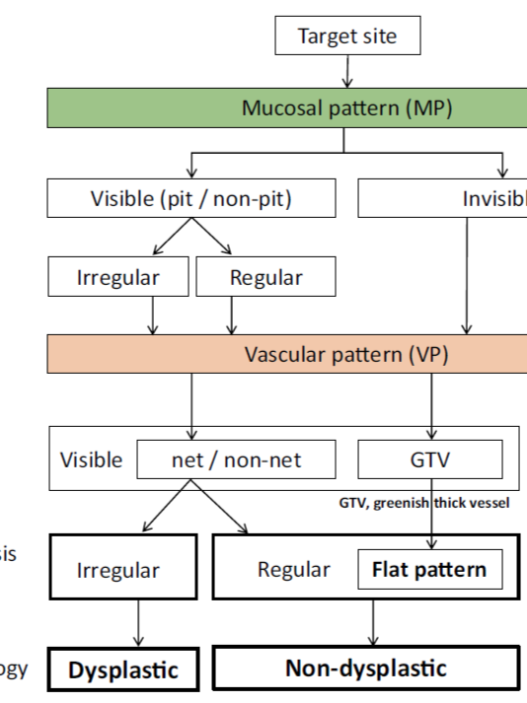

According to the morphology of the anatomical components, the MV and MS patterns were classified as regular, irregular, or absent (. Fig. 2). In principle, the MV and MS patterns must be determined separately.

DL is defined as the border between the lesion and non-lesion areas, discernible through an abrupt change in MV and/or MS patterns (. Fig. 2).

The criteria for high-grade dysplasia (HGD)/early cancer (EC) are as follows:

- Presence of an irregular MV pattern with a demarcation line.

- Presence of an irregular MS pattern with a demarcation line.

A target lesion is diagnosed as HGD/EC if it fulfills both or either of the criteria. If it does not meet either of the criteria, it is diagnosed as noncancerous.

The working group members carried out a systematic review of the English literature to determine widely accepted diagnostic systems. Consequently, the best-accepted diagnostic system was proven to be the VS classification system. Based on this system, MESDA-G was constructed using an evidence-based approach (. Figs. 3, 4, 5, and 6) [2]. First, lesions suspicious for EGC should be detected by careful inspection using conventional white-light endoscopy. Subsequently, magnified observations should be performed. Owing to the high sensitivity of the demarcation line [8], if it is absent, the suspicious lesion is diagnosed as noncancerous (. Fig. 4a, b). However, if the demarcation line is present, further assessment is required to determine the presence of an irregular MV or MS pattern. If an irregular MV and/or MS pattern is detected, the suspicious lesion is diagnosed as cancerous (. Fig. 6a, b) [1, 5, 6, 8]. If both the irregular MV and MS patterns are absent, the tumor is diagnosed as noncancerous (. Fig. 5a, b) [1, 5, 6, 8].